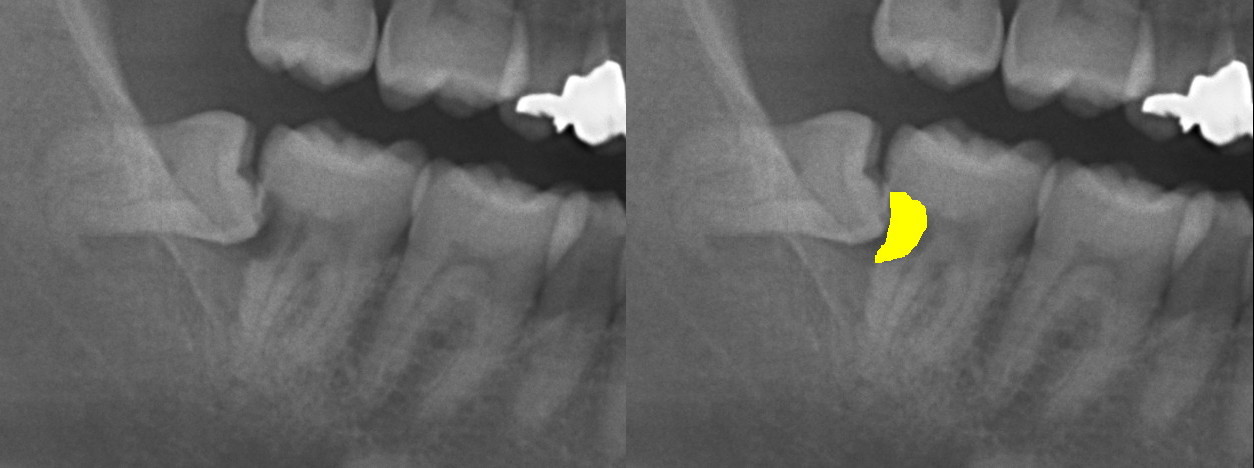

右のレントゲン写真では、青矢印が親知らず、黄色が第一大臼歯がそれぞれ虫歯になった状態を示しています。

この場合は両者を抜歯しなければなりませんでした。